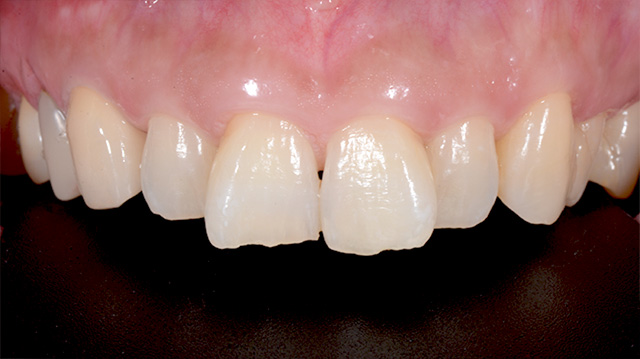

| 年代・性別 | 30代 男性 |

|---|---|

| 主訴 | 前歯の色が気になる |

| 治療期間 | 約1年 |

| 費用 |

仮歯 5,500円 × 2 ジルコニアクラウン 176,000円 × 3 インプラント 300,000円 インプラント仮歯 22,000円 サージカルガイド 70,000円 |